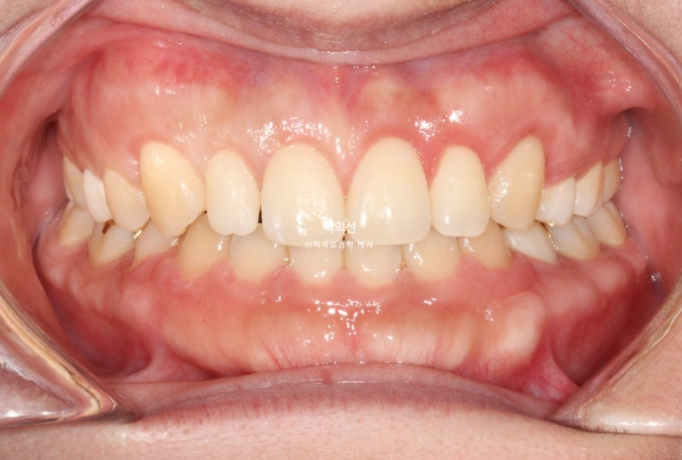

2년 전 교정치료를 위해 오신 환자분입니다.

고치고 싶은 것은 세가지 입니다.

벌어짐

비대칭

무턱

아래턱이 좌측으로 틀어져 있는 골격적 비대칭이 있고 앞니 중심선도 어긋나 있습니다.

파란화살표는 왜소치 입니다.

교정 후 라미미네이트 수복이 필요합니다.

위 앞니가 아래 앞니를 덮지 못하는 개방교합이 보입니다.